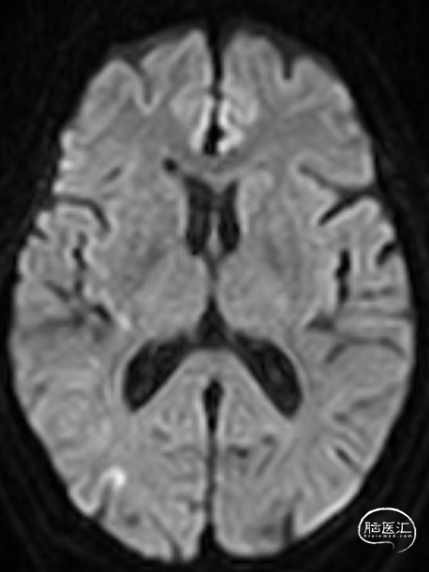

术前影像资料